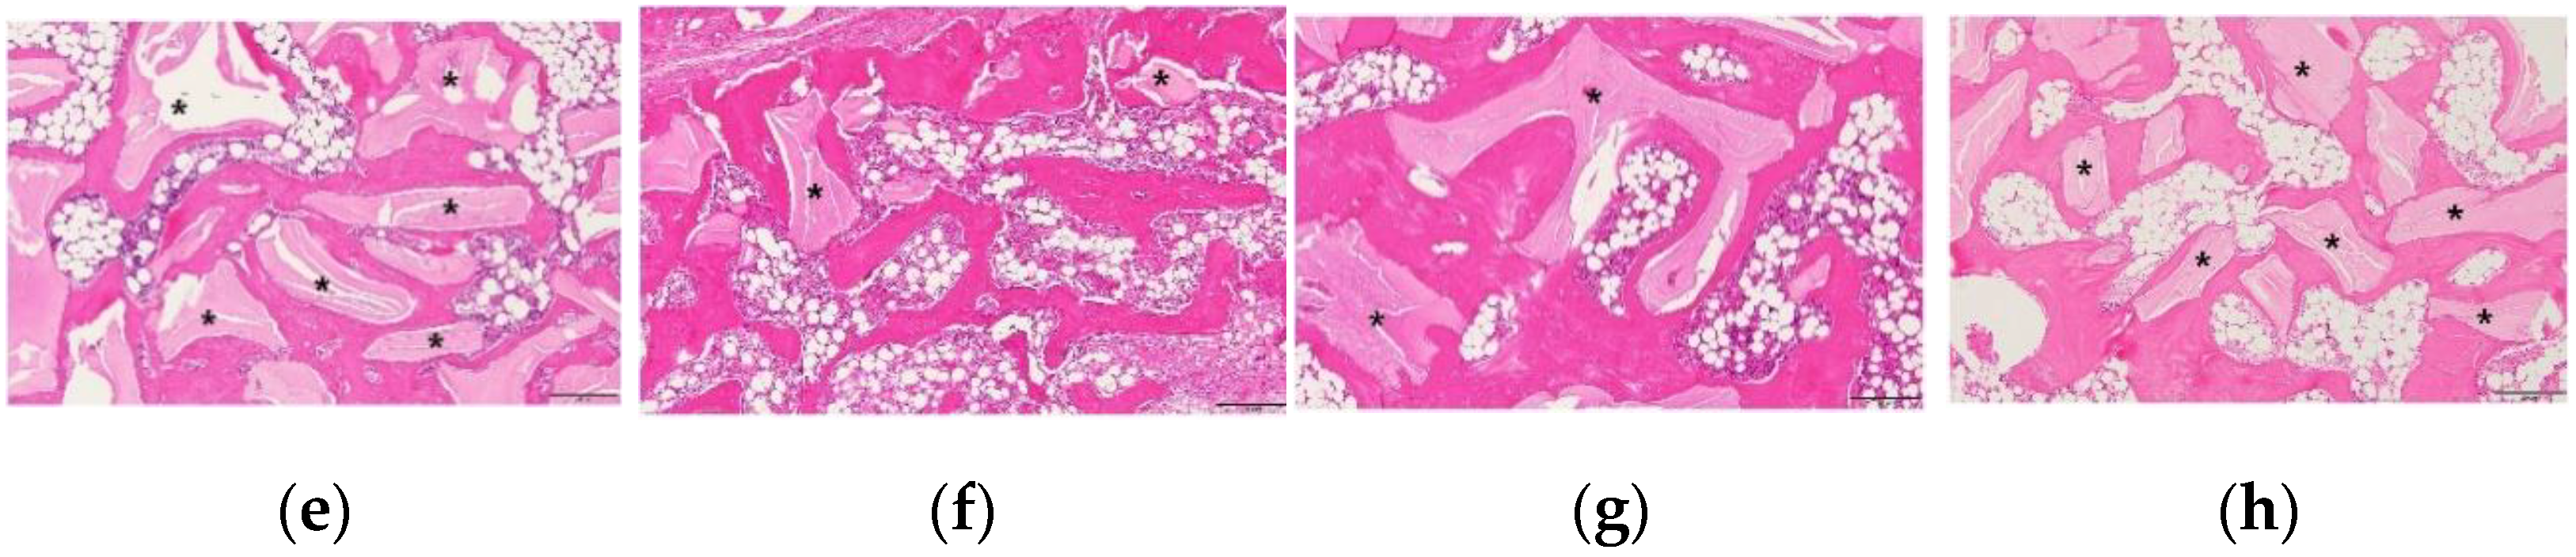

3.3. Histological Examination of the Changes in the Newly Formed Bone and Adipose Tissue